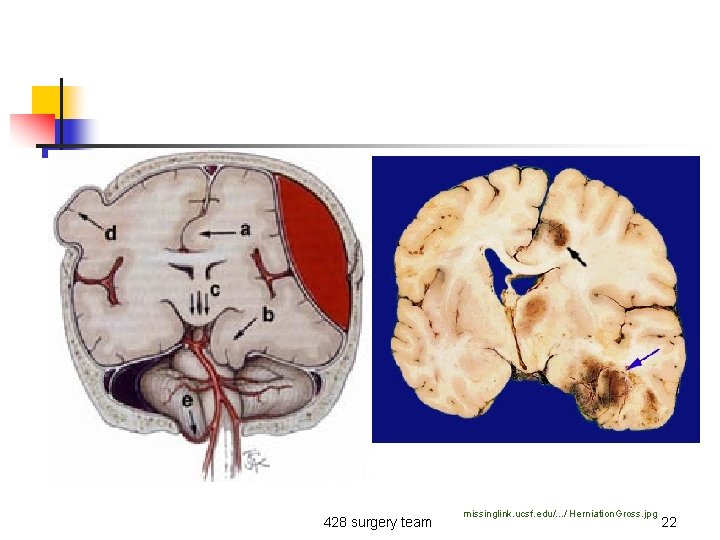

n Neurological: n n n Pupillary dilation Hemiplegia Cranial nerve deficit 428 surgery team 21

428 surgery team missinglink. ucsf. edu/. . . / Herniation. Gross. jpg 22

n If there is a mass compressing the 3 rd nerve So, ipsilateral pupil dilation and compression on the brain stem will give you contralateral hemiplasia ”weakness”. missinglink. ucsf. edu/. . . / Tentorial. Notch. Blum. jpg 428 surgery team 24

Trans-tentorial herniation: - Ipsilateral dilated pupil - Contra-lateral weakness 428 surgery team 25